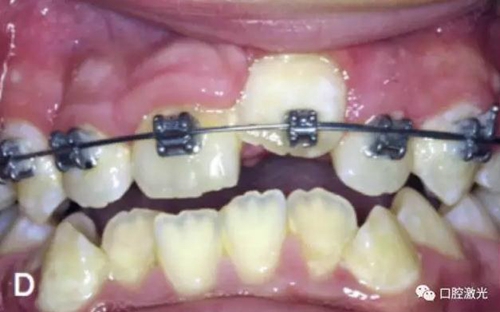

相比之下,激光開窗導(dǎo)萌有很多優(yōu)點(diǎn),如果有足夠的角化組織,那么是可以采用激光進(jìn)行開窗手術(shù)實(shí)施導(dǎo)萌,并立即粘接托槽。因此,同樣可以節(jié)省患者的等待時(shí)間。另外,口腔激光的止血特性可以提供清晰的視野,也有助于術(shù)后立即粘接托槽。

3周后效果